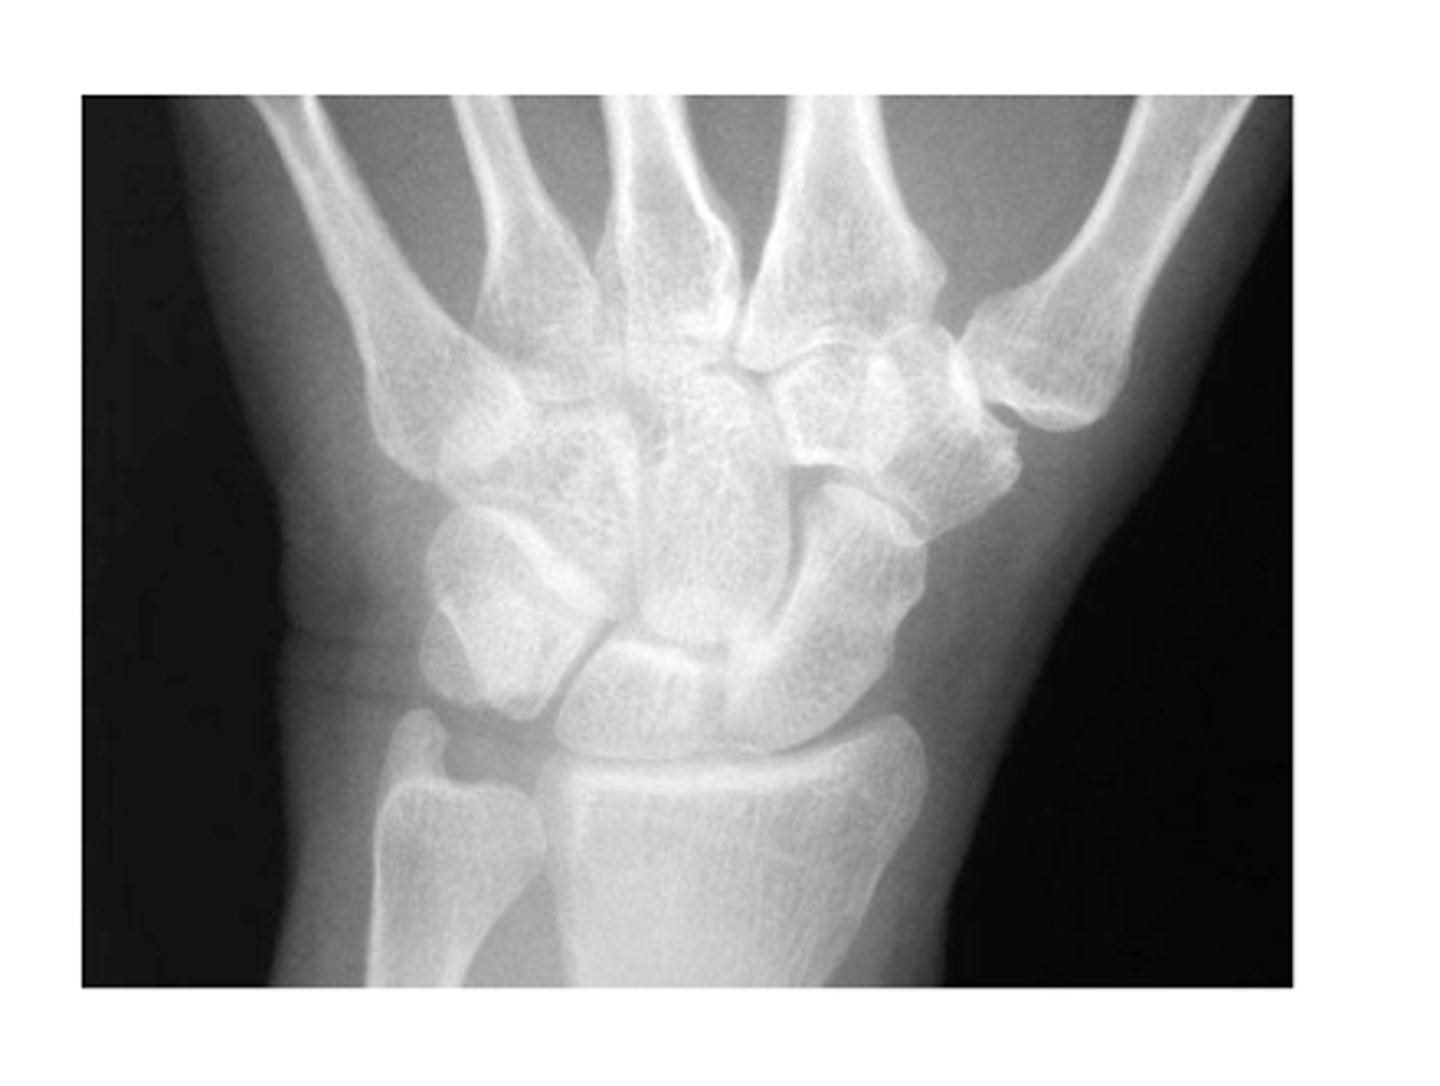

View: PA

Structure: left wrist

State the type of view and structure being depicted.